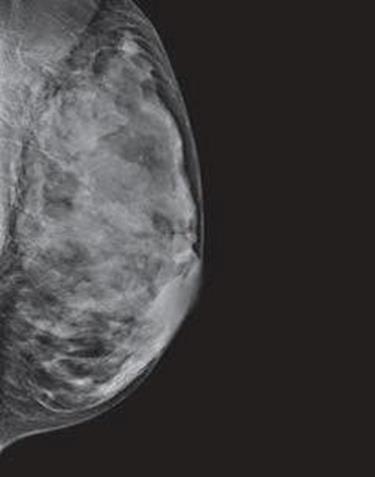

Dense breast tissue, as seen on a mammogram, has more fibrous connective tissue and glandular tissue, and less fatty tissue. It is often inherited, but menopausal hormone therapy, and low body mass index are factors associated with breast density. Dense breast tissue is a risk factor for breast cancer, and a radiologist can tell if a woman has dense breasts.

A mammogram uses X-rays (ionizing radiation) to create images of the inside of the breast to check for cancer and other conditions. It can be used for screening to detect cancer, for instance, before there’s a lump in the breast, or to assist in the diagnosis of cancer. Radiologists use mammograms to interpret, and classify breast density into four categories.

A, B, C, D’s of Breast Density and Mammograms

Dense breasts are common findings after a mammogram, and are not considered a disease, or an abnormal condition. However, they are a risk factor for a woman to develop breast cancer. According to doctors at Memorial Sloan Kettering, women with extremely dense breast tissue “are four to six times more likely to get breast cancer than people with the least dense breasts.”